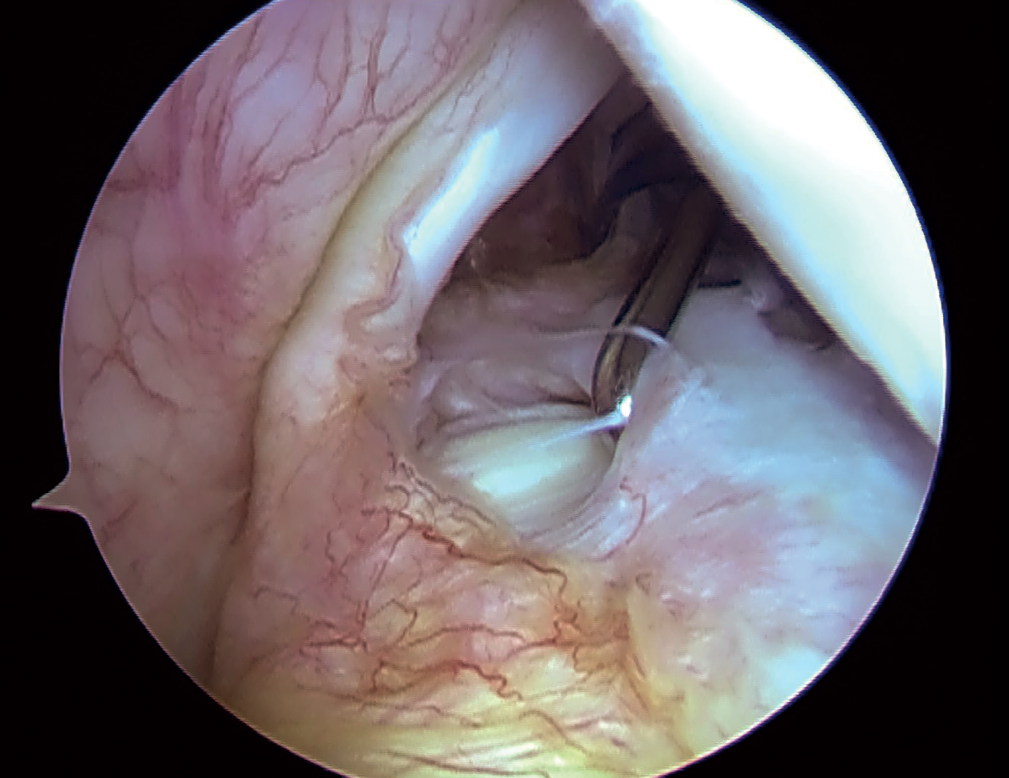

SLAP de tipo 3: desgarro en asa de cubo

Type 3 SLAP: bucket handle tear